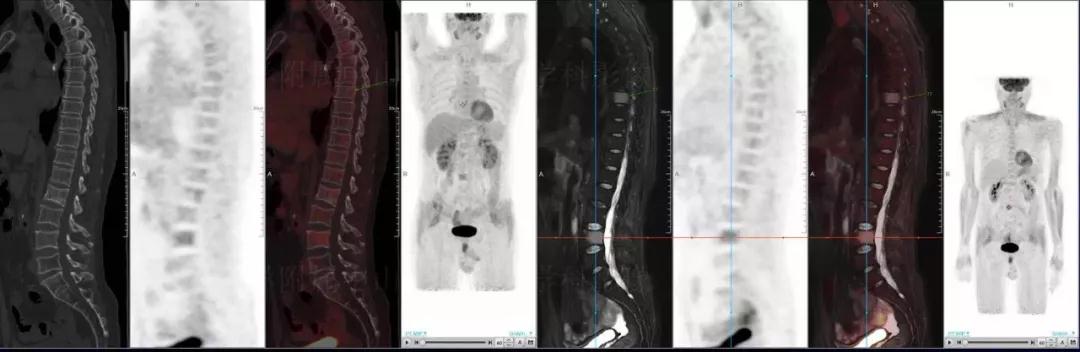

多發(fā)性骨髓瘤

中山醫(yī)院核醫(yī)學(xué)科基于聯(lián)影“時(shí)空一體”超清TOF PET/MR的融合顯像優(yōu)勢,進(jìn)行了大量的臨床掃描,發(fā)現(xiàn)多例由MGUS向多發(fā)性骨髓瘤轉(zhuǎn)變,并從中總結(jié)出了一定的共同征象,未來可能實(shí)現(xiàn)多發(fā)性骨髓瘤的早期篩查。此外,PET/MR在多發(fā)性骨髓瘤的療效評(píng)估方面,也存在顯著優(yōu)勢。

(男性,53歲。確診多發(fā)性骨髓瘤10月。經(jīng)過7周期VCD方案化療后,現(xiàn)行療效評(píng)價(jià)。)